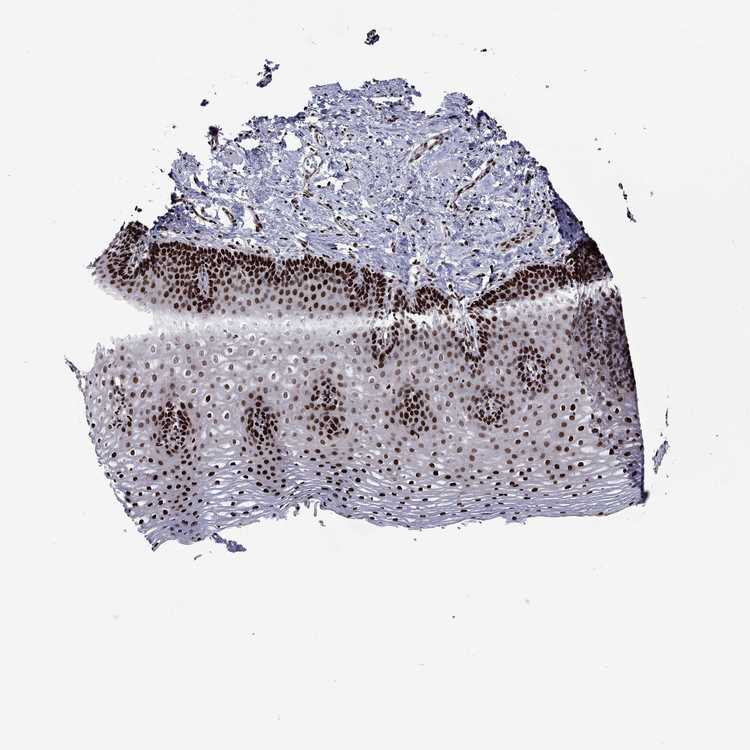

ESOPHAGUS - Antibody stainingi

Antibody staining in the annotated cell types in the current human tissue is reported as not detected, low, medium, or high, based on conventional immunohistochemistry profiling in selected tissues. This score is based on the combination of the staining intensity and fraction of stained cells.

Each image is clickable and will lead to virtual microscopy that enables deeper exploration of all samples and also displays staining intensity scores, fraction scores and subcellular localization as well as patient and tissue information for each sample.

Antibody HPA028516Antibody HPA073571

Squamous epithelial cells HighHigh